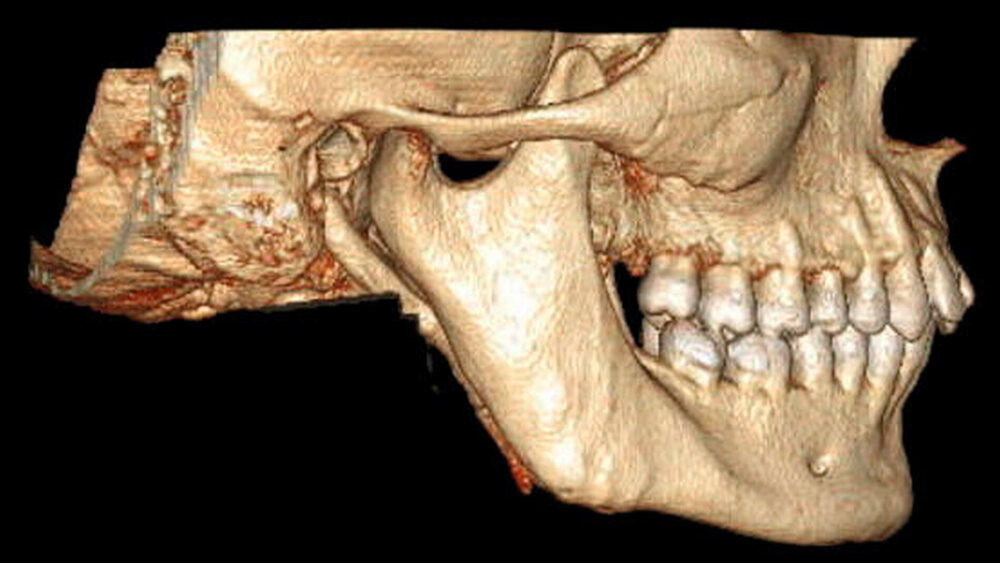

In der erweiterten radiologischen Diagnostik mittels CT zeigten sich symmetrisch angelegte Kiefergelenke beidseits ohne arthrotische Veränderungen oder signifikante Deformierungen. Ein Hinweis auf Luxation ergab sich nicht. In den axialen Schichten stellten sich beide Proc. coronoidei bis hoch in die jeweilige Fossa temporalis dar. In der 3-D-Rekonstruktion imponierten die hyperplastischen Proc. coronoidei beidseits. Diese ragten weit über die Jochbögen hinaus und schränkten dadurch die Mundöffnung ein (Abbildung 3).